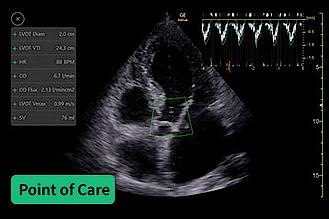

Échographie clinique en médecine d’urgence : Évaluation hémodynamique

[Formation en présentiel]

Rejoignez les Pr Xavier Bobbia, Dr Mathieu Oberlin et Dr Diane Liotier qui animeront cette session.

• Accueil des participants

Partie I | L’hypotension et l’état de choc

• Échographie dans l’état de choc non traumatique

• Atelier sur sujet sain ECMU dans l’état de choc

• Cas cliniques interactifs

• Pause Déjeuner

Partie II | La dyspnée

• Échographie dans la dyspnée

• Atelier sur sujet sain ETT de la dyspnée

• Conclusion

CESU 68 centre d'enseignement des soins d'urgence, 20 avenue Dr René Laennec, 68100 Mulhouse

Mercredi 29 avril 2026 - 9h00 - 16h30